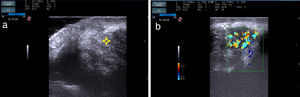

Mujer de 37 años sin antecedentes personales de interés que acude a la consulta de dermatología por una lesión en el mentón de varios meses de evolución, asintomática. A la exploración presentaba un nódulo marronáceo, de 2cm de diámetro, de consistencia elástica (fig. 1). La paciente no presentaba adenopatías palpables. Se realizó la extirpación quirúrgica de la lesión. En el estudio histológico se evidenció una epidermis sin alteraciones, con presencia en las capas profundas de vasos recubiertos por células endoteliales de aspecto epitelioide, agregados linfocitarios y eosinófilos (fig. 2 A y B). En la analítica se detectó eosinofilia, sin alteraciones en el resto de las determinaciones de laboratorio. Con los hallazgos obtenidos se realizó el diagnóstico de HALE. Durante toda la evolución se ha realizado seguimiento ecográfico (Esaote My Lab One, sonda líneal de frecuencia variable 18-22MHz, resolución lateral 240micras), objetivándose una masa de bordes mal delimitados en la dermis, compuesta por haces hiperecoicos e hipoecoicos entrelazados, formando una imagen en «ovillo de lana» (fig. 3 A), rodeada por un halo hiperecoico. En el estudio doppler (Esaote My Lab One, sonda líneal, modo power doppler, frecuencia 18MHz, PRF 750MHz) se evidenció un aumento de vascularización (fig. 3 B). Esta imagen se ha mantenido sin cambios a pesar de los tratamientos realizados.

A. Imagen ecográfica de la lesión: nódulo mal delimitado en la dermis, con haces hiperecoicos e hipoecoicos, formando una imagen en «ovillo de lana» (señalado mediante asterisco). B. Doppler color de la lesión, donde se objetiva hipervascularización. Nótese también la presencia de un halo hiperecoico rodeando la masa (señalado mediante asterisco).